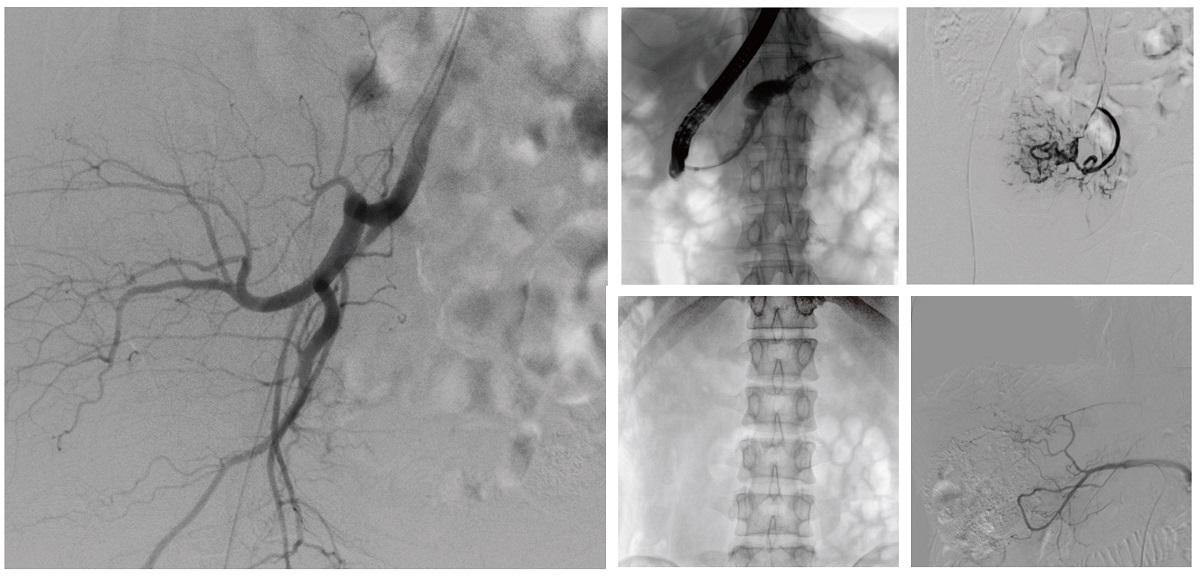

醫(yī)院引進的普愛醫(yī)療移動式平板介入中C,其高清成像能力覆蓋骨科、介入科、泌尿外科、婦產(chǎn)科等多科室,能夠滿足介入微創(chuàng)手術(shù)的多樣化需求。

設備的移動式設計,無需對現(xiàn)有手術(shù)室進行改造,適合高負荷手術(shù)量或應急情況下的靈活部署。如在急診介入手術(shù)中,該設備能迅速響應需求,為醫(yī)生提供實時影像支持,提升搶救效率。